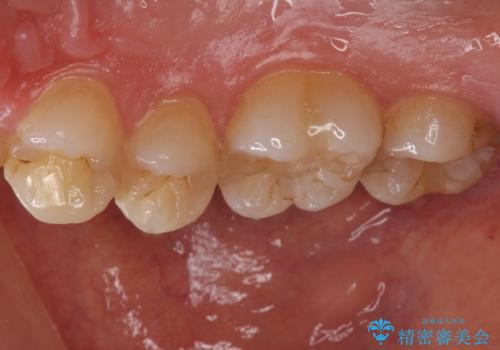

- 歯の健診にて来院。

レントゲンを撮った時にう蝕があったため、拡大鏡下でう蝕が残っていないか確認し

セラミックの詰め物(e-maxインレー)にて治療を行いました。

- e-maxインレー 7.7万円 ×2本費用は治療当時の料金となります